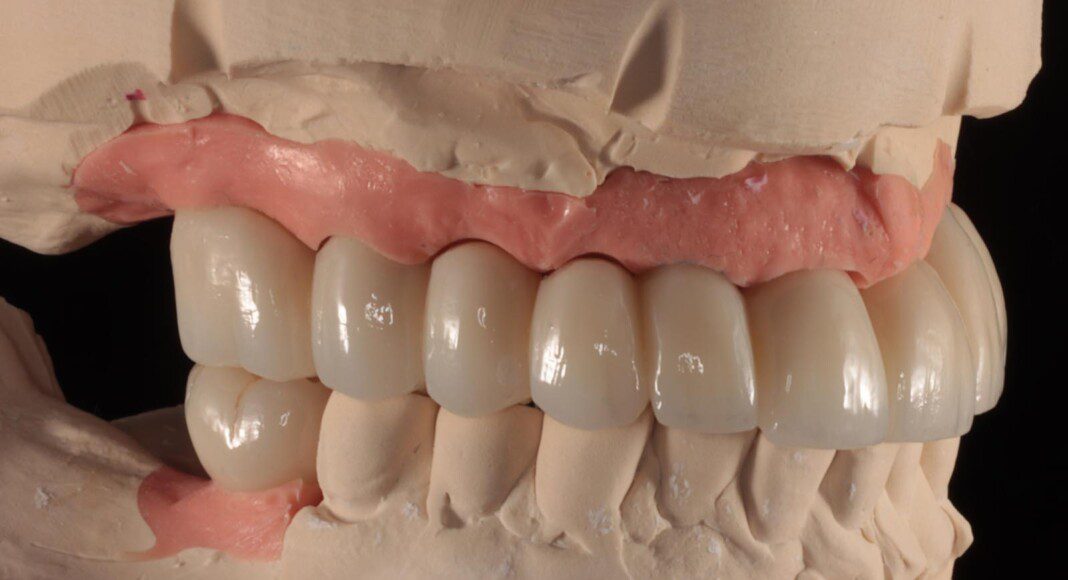

Prototype try-in. This patient was much more particular than we expected. Therefore, we made a very detailed prototype for everyone to evaluate closely. Pictures taken from all angles.